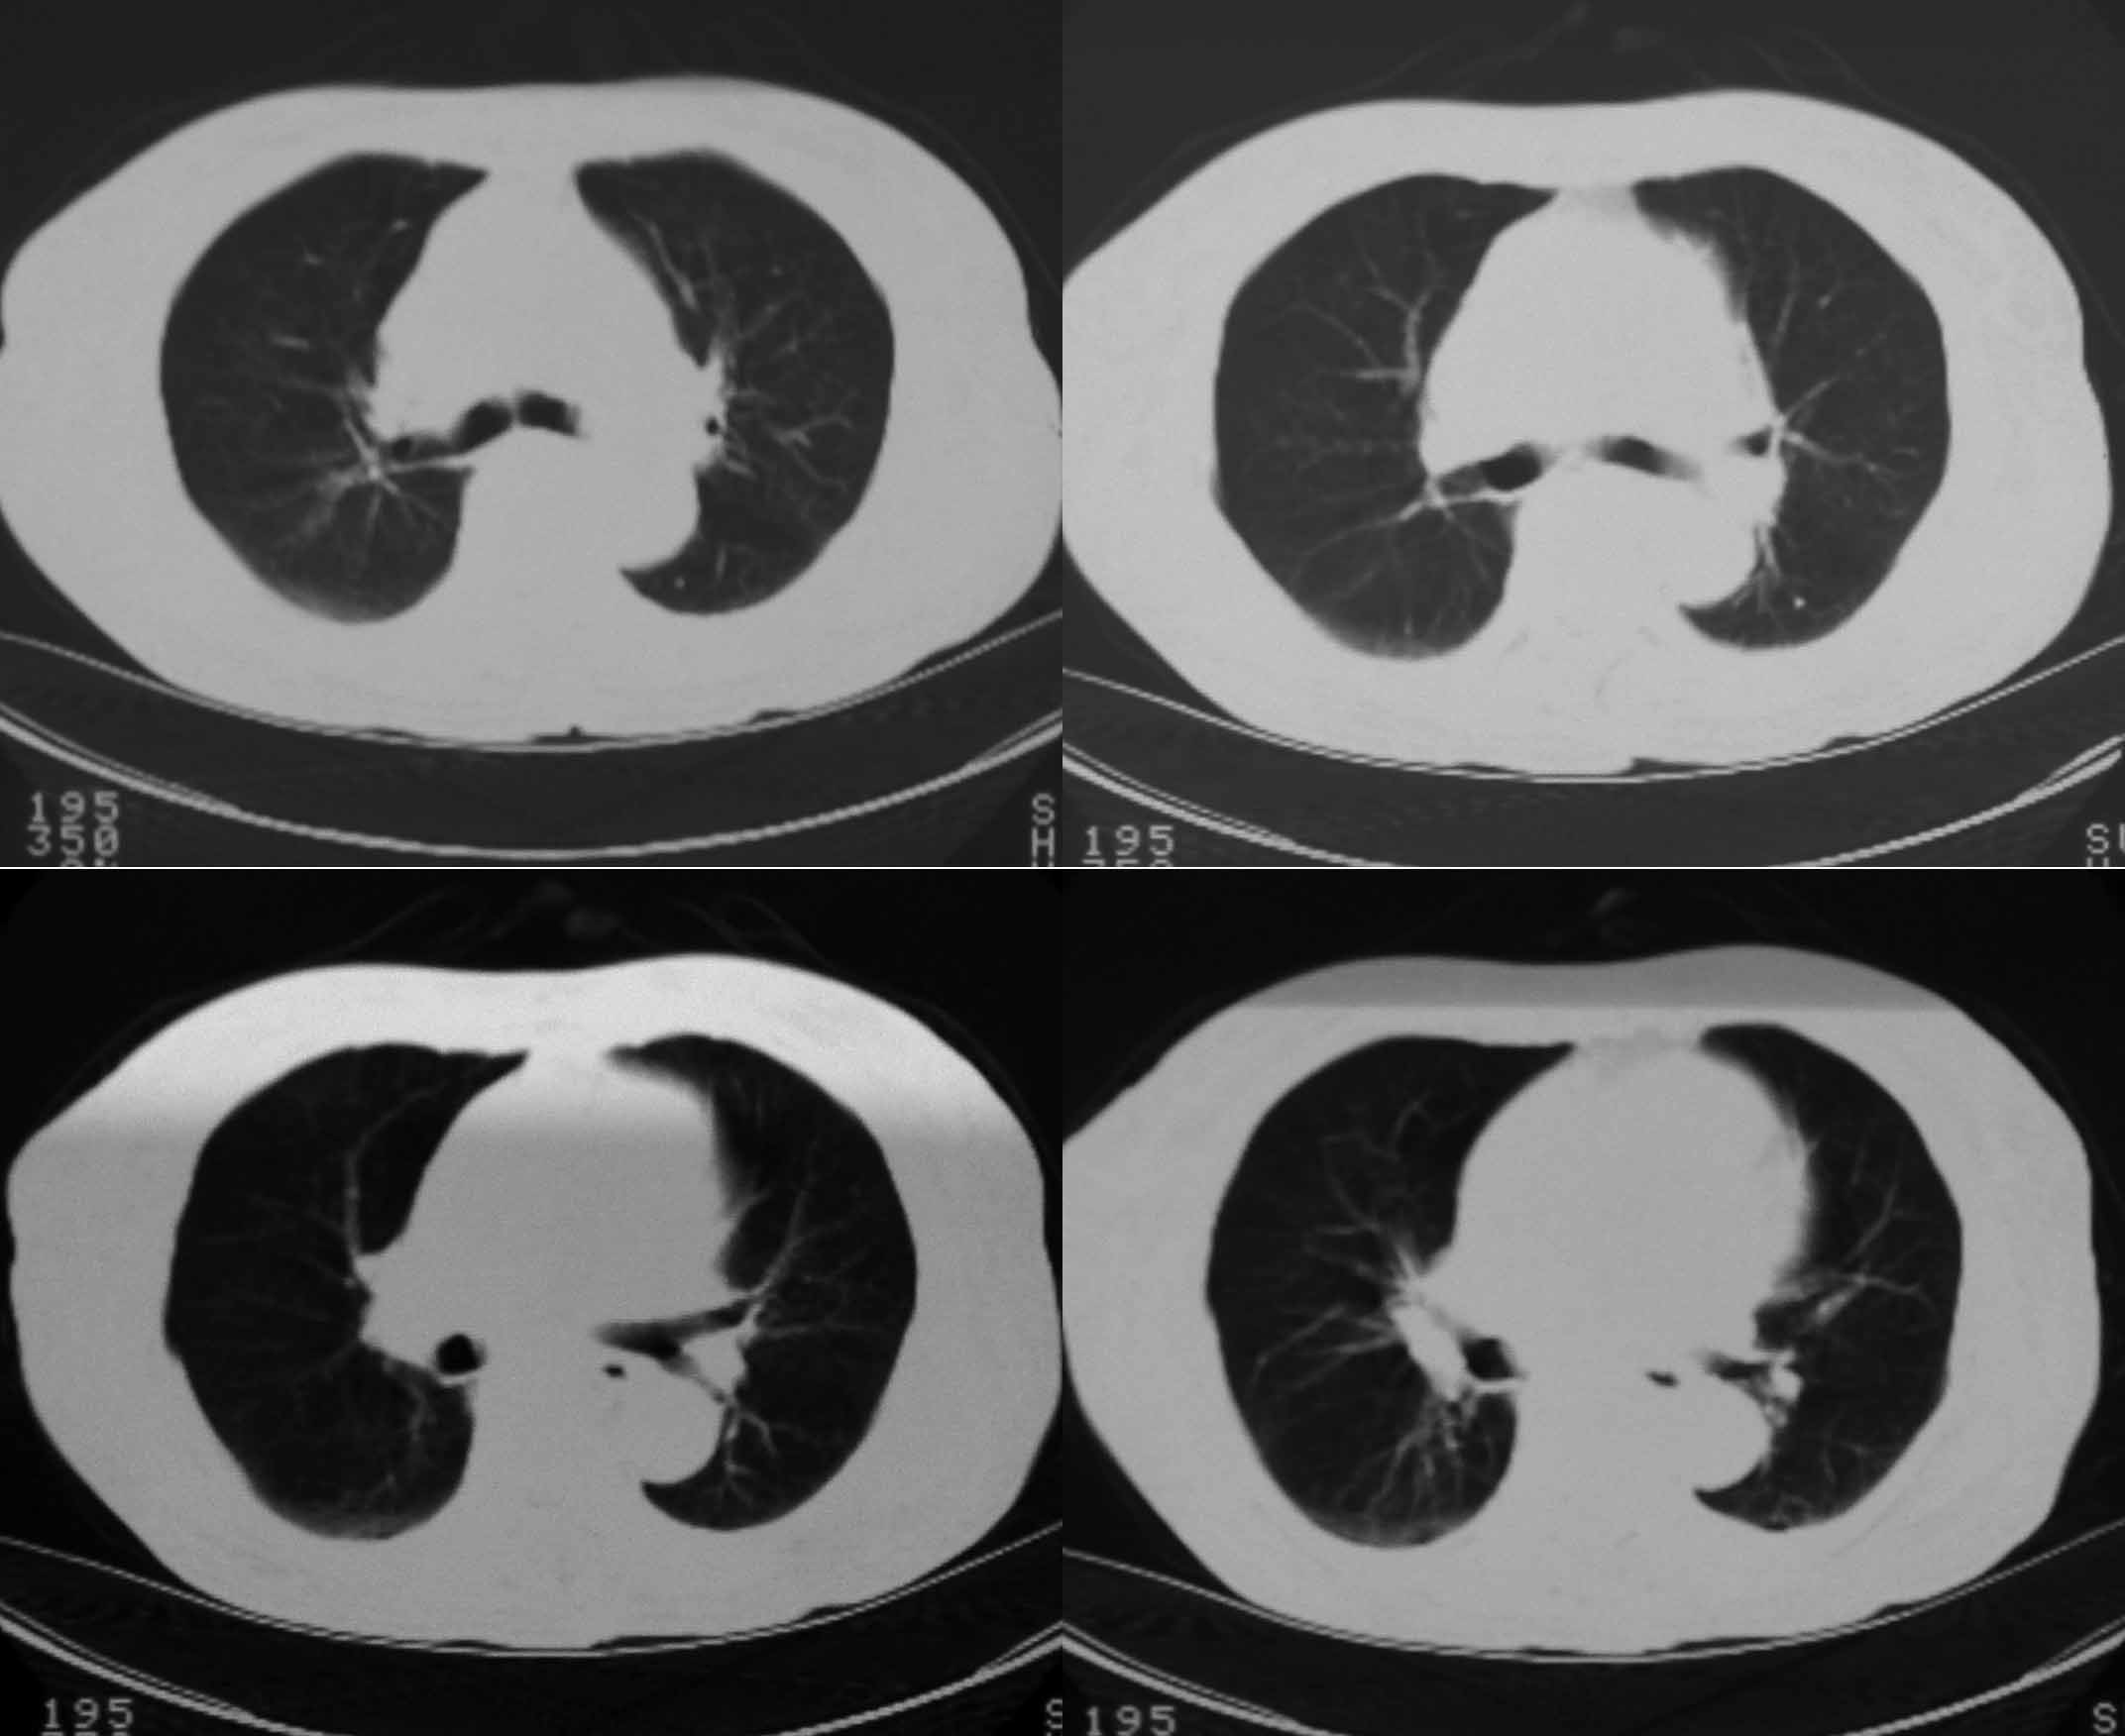

女69岁。时有咳漱、咳白色痰请老师们看看箭头所指是什么?ct值约-36.报告应该怎样写?谢谢!

说实话,图像质量一般,楼主所指为局部胸膜肥厚表现

楼主所指为局限性胸膜肥厚

楼主所指为局限性胸膜肥厚  ct值是因为肺窗

局限性胸膜肥厚  ct值有时也不准

局限性胸膜肥厚,心影增大,建议心超检查